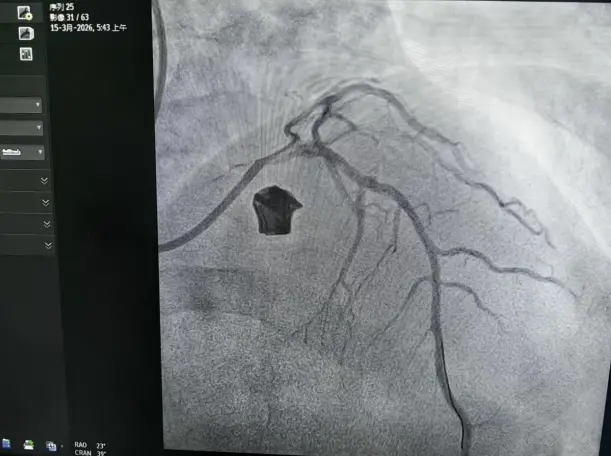

整个手术过程中,吕国辉带领着介入团队精准操作,利用冲击波球囊释放的声波能量,精准击碎血管内360度环形坚硬钙化斑块,在不损伤血管内膜的前提下,成功将钙化的血管“松绑”扩张,打通了堵塞的冠脉血管,为老奶奶顺利完成治疗。

术后影像

术后第二天,老奶奶的胸痛、胸闷、气短等症状得到了改善,轻度活动时不再出现不适,老奶奶的脸上重新露出了久违的笑容。